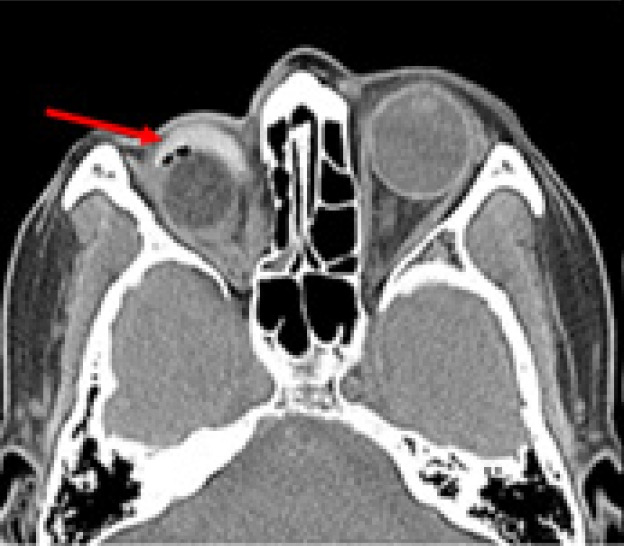

Orbital floor fractures are commonly encountered, but the dislocation of the eyeball into the maxillary sinus is relatively rare. When it does occur, globe dislocation can have serious consequences, including vision loss, enucleation, and orbito-ocular deformity. Immediate surgical intervention is typically attempted when possible. However, severe comorbidities and poor general health can delay necessary surgery. In this report, we present the surgical outcomes of a 70-year-old woman who received delayed treatment for traumatic eyeball dislocation into the maxillary sinus due to a subarachnoid hemorrhage and hemopneumothorax. Additionally, we propose a treatment algorithm based on our clinical experience and a review of the literature.